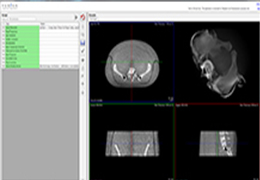

Traditional multi-planar slicing

High-quality and fast 3D reconstruction and 3D rendering

Multi-planar slicing.

Oblique slicing.

Axis-aligned cropping with context.